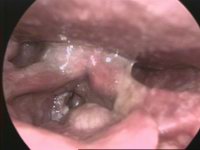

咽喉炎图片和正常图片 自己排除喉癌的方法 帮助信息 动天数据